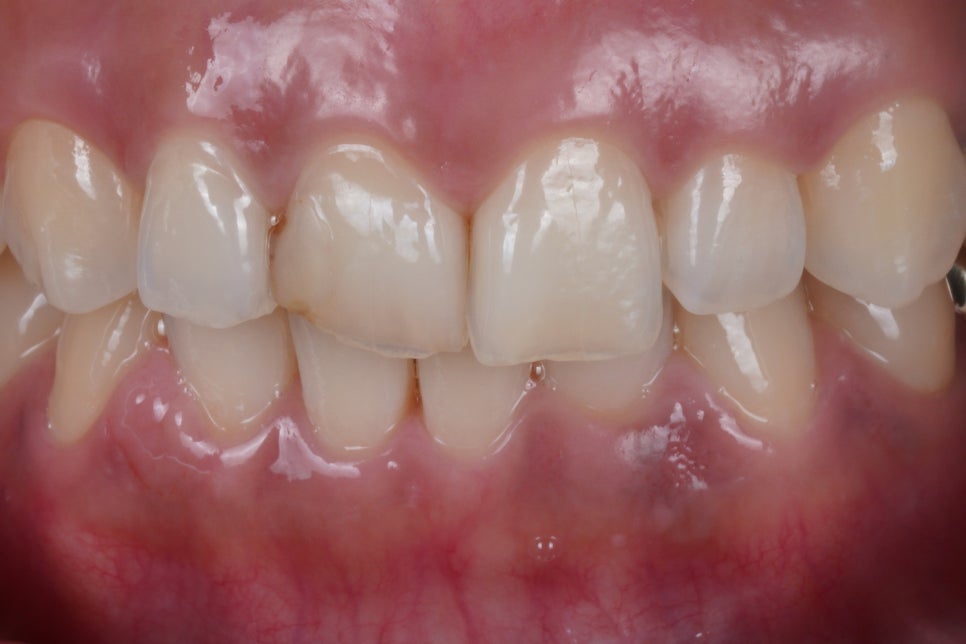

예전에 앞니 레진 받은 부위가 깨져나가서 다시 해야겠다고 고민하시던 차에 여러모로 검색해보시고, 고민해보시다 저희를 찾아주셨다고 합니다. 기존에 해놨던 부분은 특히 옆니와 앞니 사이 레진이 서로 붙어있어 치실질이 되지 않았고, 때문에 옆니에도 충치가 생겨있었는데요. 그점도 이미 알고계셔서 함께 수복하기로 했습니...

출처 아카이브 열기예전에 앞니 레진 받은 부위가 깨져나가서

다시 해야겠다고 고민하시던 차에

여러모로 검색해보시고, 고민해보시다

저희를 찾아주셨다고 합니다.

기존에 해놨던 부분은 특히

옆니와 앞니 사이 레진이 서로 붙어있어

치실질이 되지 않았고,

때문에 옆니에도 충치가 생겨있었는데요.

그점도 이미 알고계셔서

함께 수복하기로 했습니다.

그 결과, 이렇게 자연스럽게 되었어요.

앞니는 제가 유명해진 이유이자 잘하는 진료인

Direct Composite Veneer 입니다.

역시나 자연치아가 가진

고유의 그라데이션

<투명층>도 재현해드렸습니다.

치아 사이즈도 잘 맞춰 드렸고요.